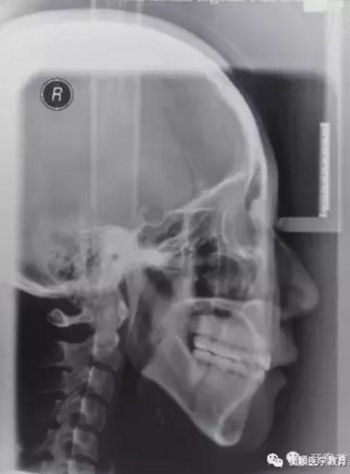

圖6 治療后頭顱側(cè)位片